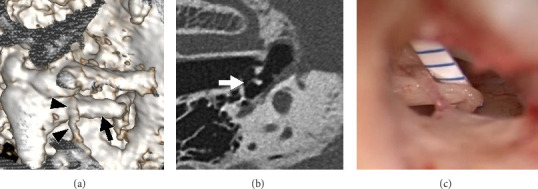

Objective: This study evaluated the sensitivity and accuracy of ultra-high-resolution computed tomography (U-HRCT) in predicting the relationship between the chorda tympani and the long crus of the incus in patients with otosclerosis or middle ear anomalies. Methods: Thirteen patients with otosclerosis or middle ear anomalies were enrolled in this study (three males and ten females; mean age, 41.6 years; range, 7-67 years). The patients underwent U-HRCT (Aquilion Precision; Canon Medical Systems, Japan). Multiplanar reconstruction images were obtained, and the distance between the chorda tympani and the long crus of the incus was measured in a plane parallel to the superstructure of the stapes. In addition, the distance between the two structures was measured during surgery. Subsequently, distances of every 0.5 mm obtained using the two modalities were grouped and compared. Results: The U-HRCT-based evaluation revealed that the mean distance from the chorda tympani to the long crus of the incus was 0.7 mm, whereas the mean actual distance during the surgery was 0.9 mm. In nine of the 13 patients, the U-HRCT-based and actual distances belonged to the same group. In four patients, the U-HRCT measurements were smaller than the actual distances. The chorda tympani was attached to the long crus of the incus in three cases, and U-HRCT precisely predicted this finding in all three cases. Conclusion: U-HRCT is useful for detecting the relationship between the chorda tympani and the long crus of the incus in patients with otosclerosis or middle ear anomalies.